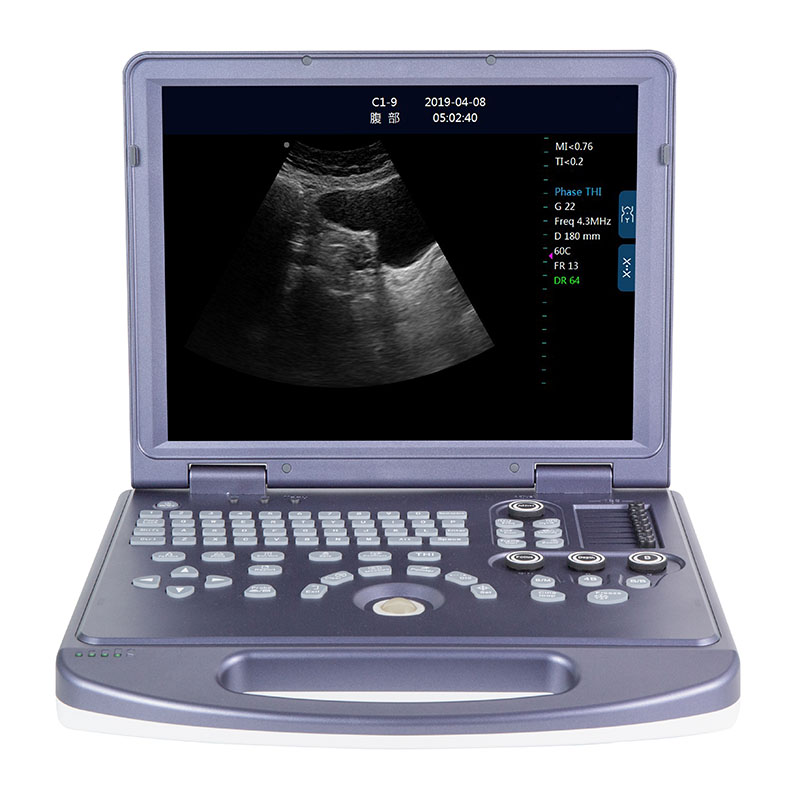

Máquina de ultrasonido portátil en blanco y negro RC-BW580

El ultrasonido portátil RC-BW580 es un equipo diagnóstico confiable diseñado para ofrecer imágenes precisas en una amplia variedad de entornos clínicos. Con una pantalla LED de 12 pulgadas y modos de imagen versátiles, como B, 2B, 4B, M y B&M, permite evaluar estructuras anatómicas con claridad y eficiencia. Su sonda multifrecuencia proporciona un rango de aplicaciones clínicas, desde abdomen y obstetricia hasta tejidos blandos y exploraciones musculoesqueléticas.

El RC-BW580 está equipado con reconocimiento de 65 marcas corporales, lo que facilita una mayor exactitud durante el examen y mejora el flujo de trabajo del profesional. Su batería de larga duración (3–5 horas) lo convierte en una solución ideal para clínicas móviles, consultorios, zonas rurales y atención domiciliaria.

La portabilidad del sistema, junto con sus puertos USB y entradas para sondas adicionales, garantiza flexibilidad y compatibilidad con diferentes configuraciones clínicas. Su diseño intuitivo y soporte multilingüe permiten un uso sencillo incluso en entornos de alta demanda. En conjunto, el RC-BW580 es una herramienta esencial para médicos y especialistas que requieren un ultrasonido práctico, eficiente y accesible.

El RC-BW580 es una máquina de ultrasonido portátil en blanco y negro diseñada para ofrecer diagnóstico eficiente en diversos entornos clínicos. Cuenta con una pantalla LED de 12 pulgadas, modos de imagen versátiles (B/2B/4B/M/B&M) y soporte multilingüe, lo que facilita su uso en distintos escenarios médicos. Su sonda multifrecuencia y capacidad para reconocer 65 marcas corporales permiten obtener imágenes precisas. Además, su batería de larga duración (3-5 horas) y puertos USB y de sonda hacen que sea una herramienta portátil y confiable para profesionales de la salud.